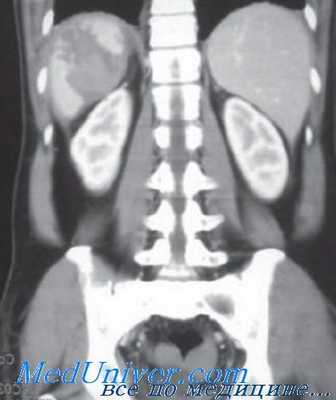

Доктора Demetriades и Velmahos наметили несколько критических пунктов, достойных, на мой взгляд, повторного упоминания. Во-первых, ABCDs и клинический осмотр — самые важные элементы в оценке травмированного пациента. В современной диагностике нередко представляется, что КТ полностью вытеснила клиническое обследование. КТ служит лишь дополнением первичной оценки, а не компонентом начального обследования.

Наличие перитонита или гемодинамической неустойчивости вызванные травмой живота являются показаниями к экстренной лапаротомии, а промежуточная КТ просто ставит жизнь пациента под угрозу — помните, что смерть начинается с лучевой диагностики.

Во-вторых, использование целенаправленного УЗИ живота при травме (FAST) должно быть основано на каждодневном опыте конкретного учреждения. В центрах с большой нагрузкой и врачами, обученными его использованию, FAST играет важнейшую роль в оценке пострадавшего.

Пациенты с положительным обследованием FAST и гемодинамической нестабильностью быстро транспортируются в операционную, в то время как при устойчивом состоянии для уточнения ситуации выполняется КТ. Хотя отрицательные результаты FAST обычно допускают наблюдение за пациентом, это не означает, что отрицательный FAST у нестабильного пациента надежен.

У пациентов с гипотензией вследствие травм живота вначале возможен отрицательный результат FAST, потому что для четкого обнаружения полосы жидкости в кармане Моррисона нужно, чтобы в брюшной полости набралось 300-400 мл крови. С восстановлением объема жидкости и увеличением кровяного давления пациента, кровотечение из паренхиматозных органов или брыжеек приводит к положительному FAST Поэтому при нестабильном состоянии обязательно повторное обследование FAST.

Кроме того, устойчивые необъяснимые гемодинамические нарушения, несмотря на отрицательный FAST, требуют диагностической аспирации из брюшной полости (ДАБП), чтобы исключить брюшную полость как источник геморрагического шока.

В-третьих, несмотря на доступность КТ и ее незаменимую роль в лечении закрытых повреждений паренхиматозных органов, существуют и ограничения. Авторы хорошо проиллюстрировали ненадежность метода для диагностики повреждений полых органов или брыжеек. Типичные косвенные признаки повреждений включают свободную жидкость без повреждения паренхиматозного органа, «затемнение» или «штриховку» брыжейки и утолщение кишки.